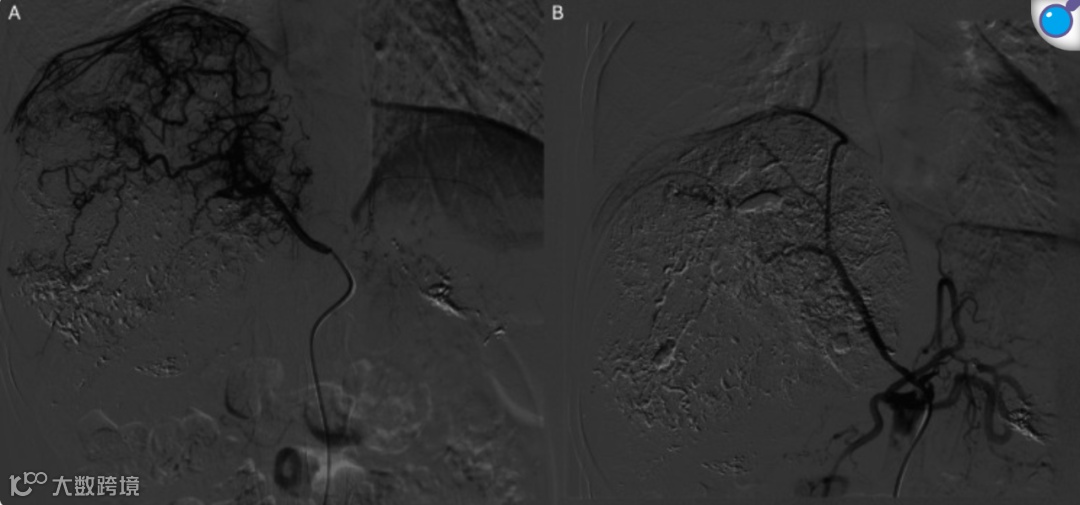

术中血管造影显示肿瘤由右肝动脉及右下肺静脉供血,使用碘油及药物洗脱微球进行栓塞(图2)。术后约15分钟,患者主诉双下肢突发麻木。考虑脊髓缺血,立即请神经科会诊,并予大剂量甲基泼尼松龙治疗(初始30 mg/kg静脉推注,随后5.4 mg/kg/h持续输注23小时)。神经外科会诊后认为无减压手术指征。

图2. 右下肺静脉数字减影血管造影(DSA)。A. 右下肺静脉选择性血管造影显示肿瘤高度血管化,由该动脉供血;B.栓塞后血管造影显示大部分肿瘤供血分支成功闭塞。